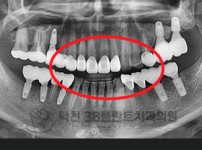

치료전후